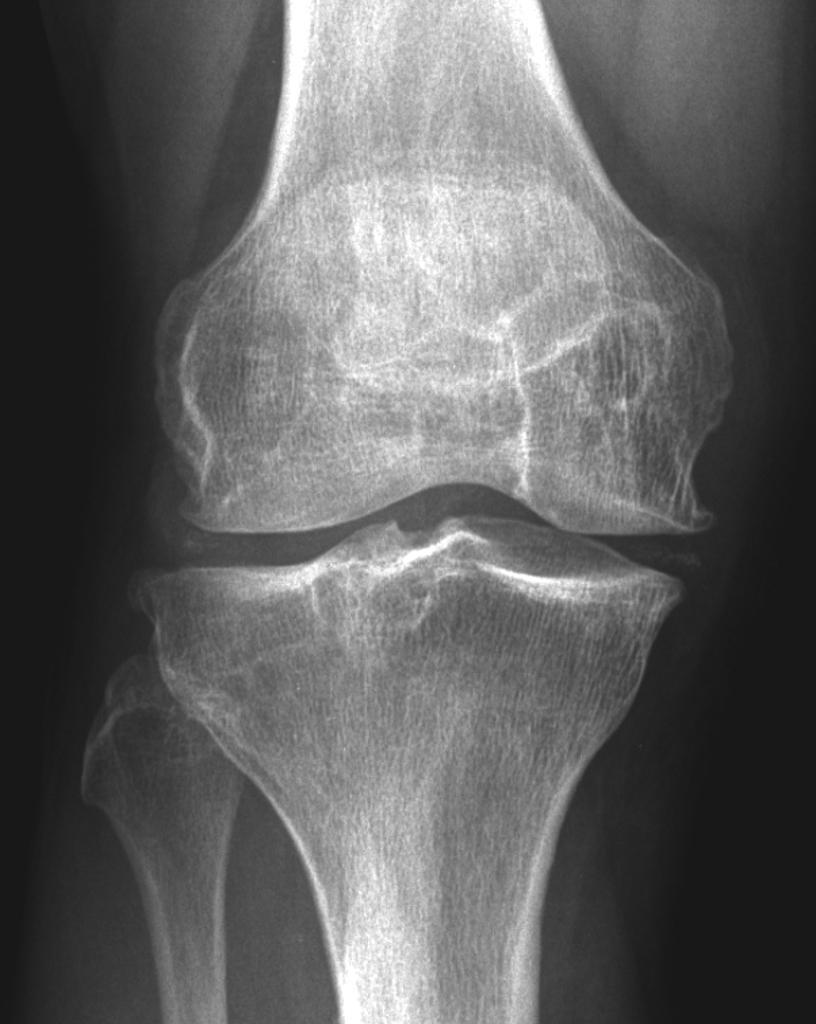

Chondrocalcinosis is a key feature of which condition? What is it?

Calcium pyrophosphate deposition disease

Calcification of hyaline cartilage seen on x-ray → often asymptomatic